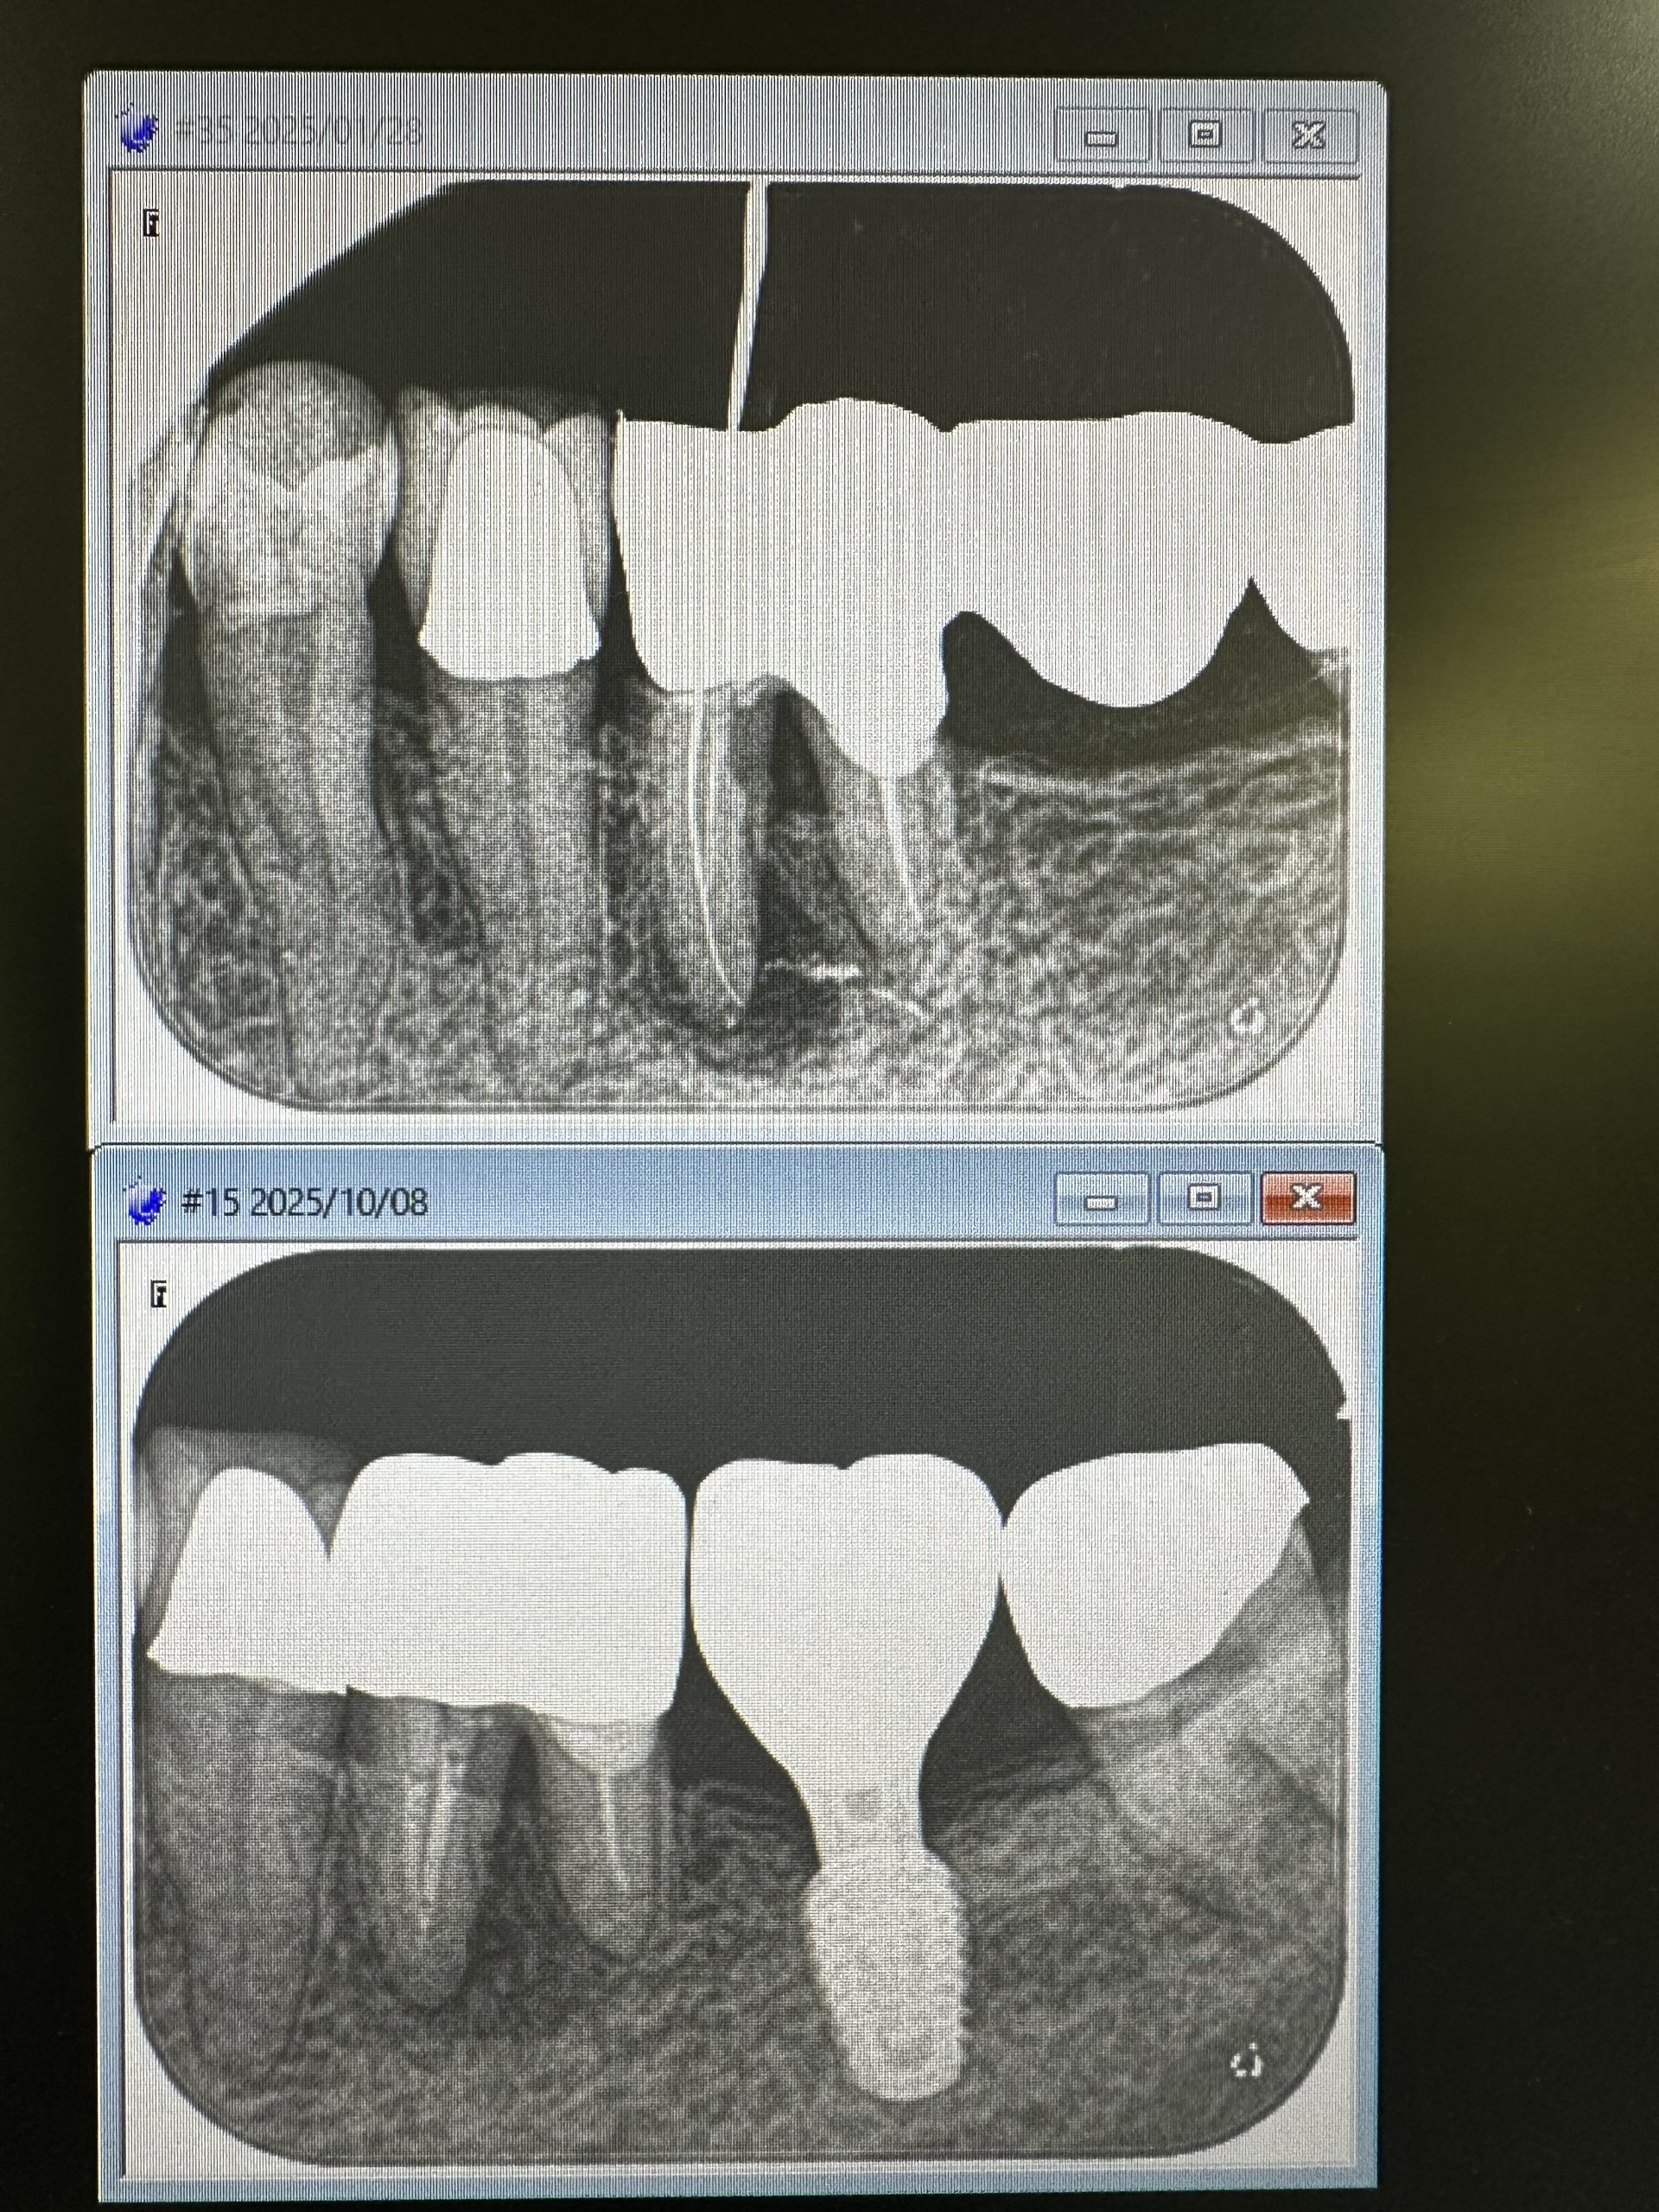

根尖病巣に分岐部病変あるブリッジ

負担荷重の兆候

単独処理、根管治療、分岐部処置にヤグレーザー

だいぶ分岐部が改善されてきている💪

病巣も!

大臼歯ブリッジ幅10から11ミリあり負担MAX、無論入れ歯も良くない👎